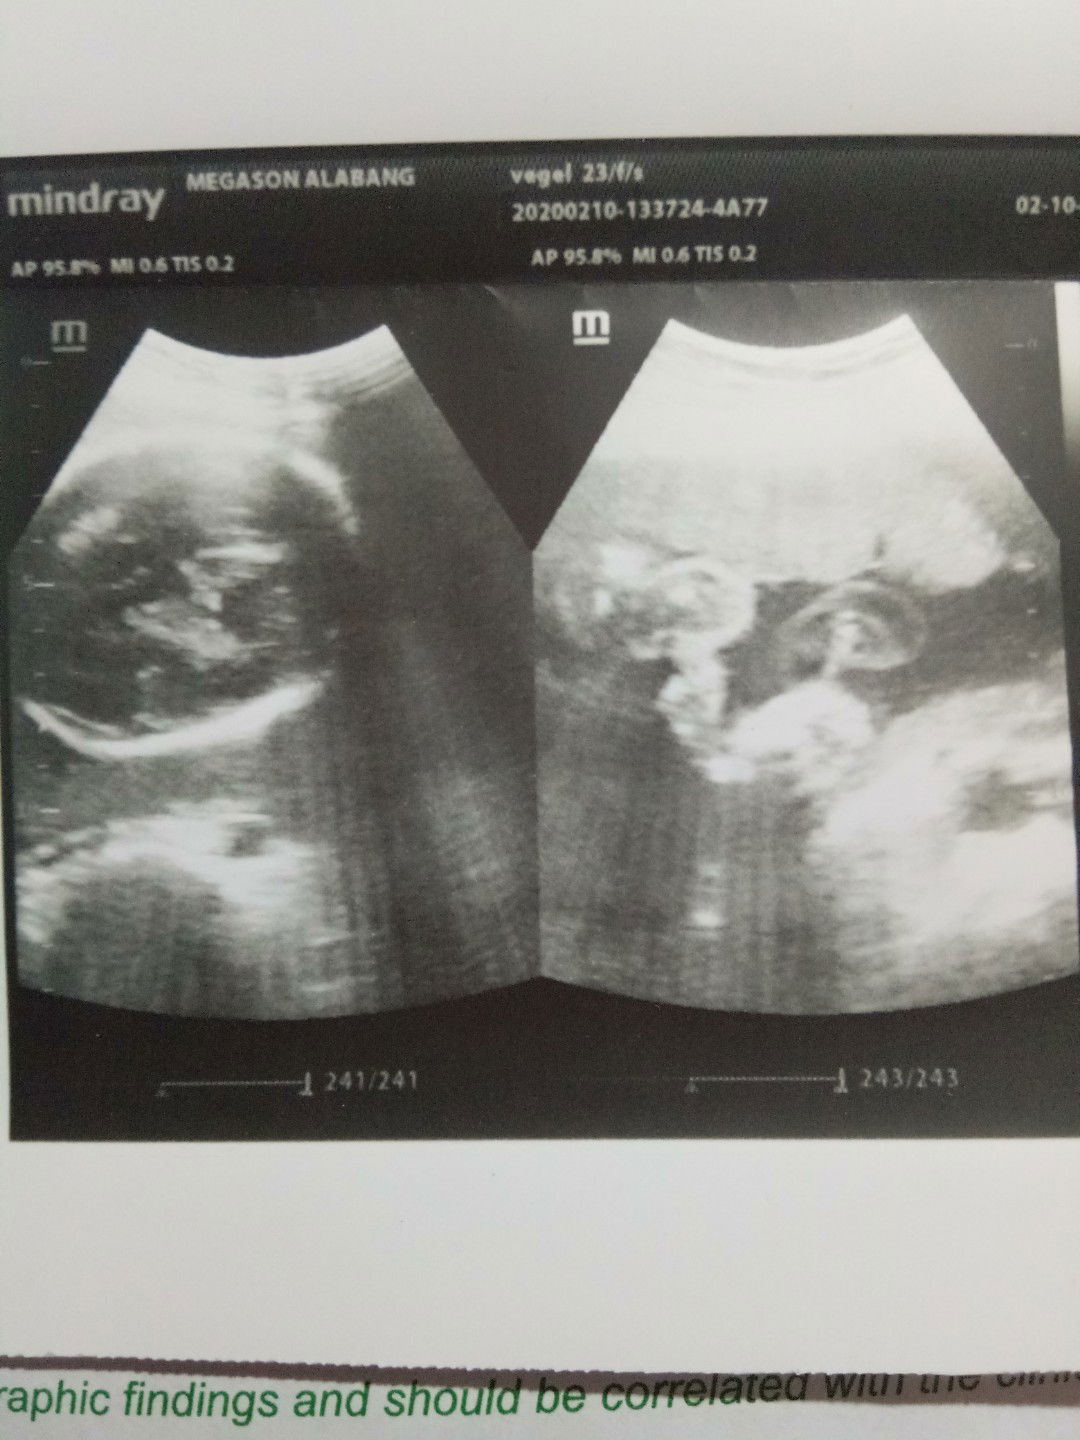

ask ko lang po anu po kaya gender baby ko 27 weeks napo

girl po ba or boy dipo kasi ako marunong tumingin sa ultrasound respect po sana thank u po

Usually matutukoy ng ultrasound machine if it's a girl or boy. Yung sa ultrasound ko may nakalagay boy.